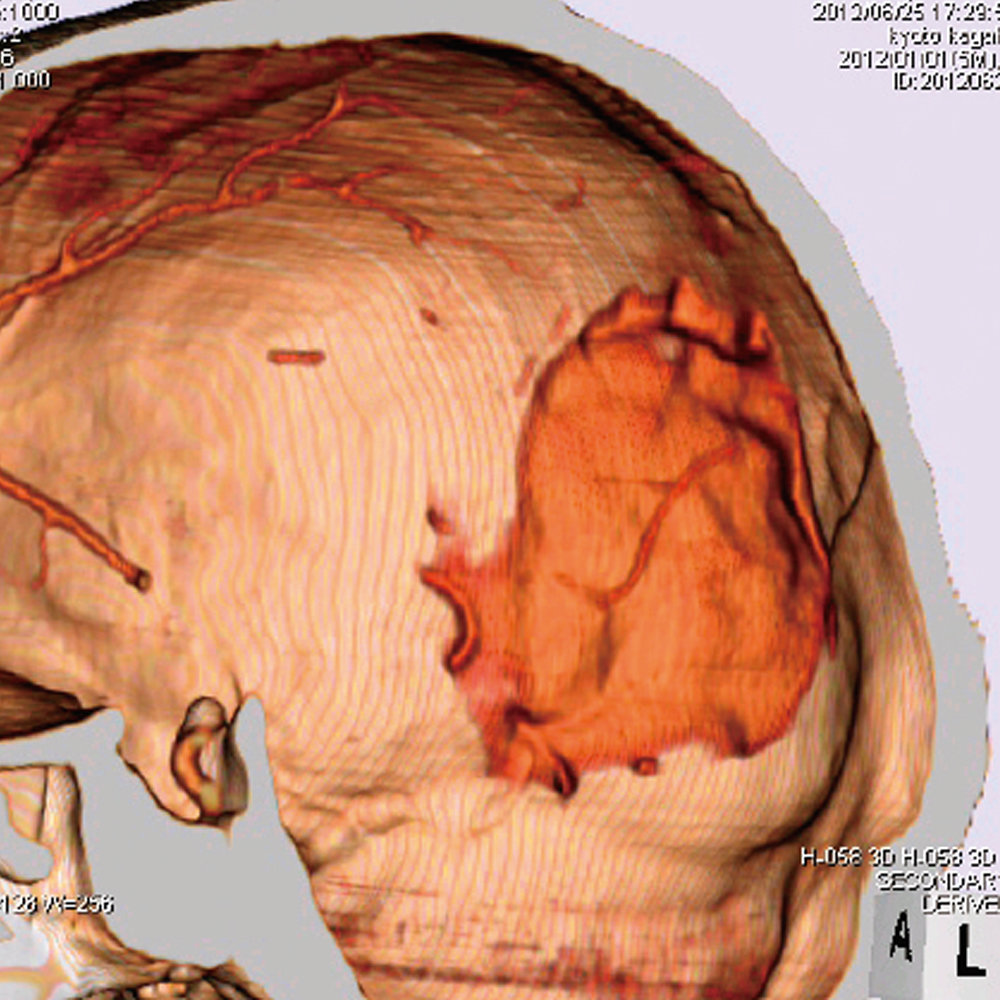

CT Whole Body Phantom - With Pathologies

1A unique, life size whole body phantom for CT provides a variety of educational application as well as visual evaluation in finding out optimal scanning conditions

| Case / Pathology | Refer to PDF( Anatomy and Pathologies) |